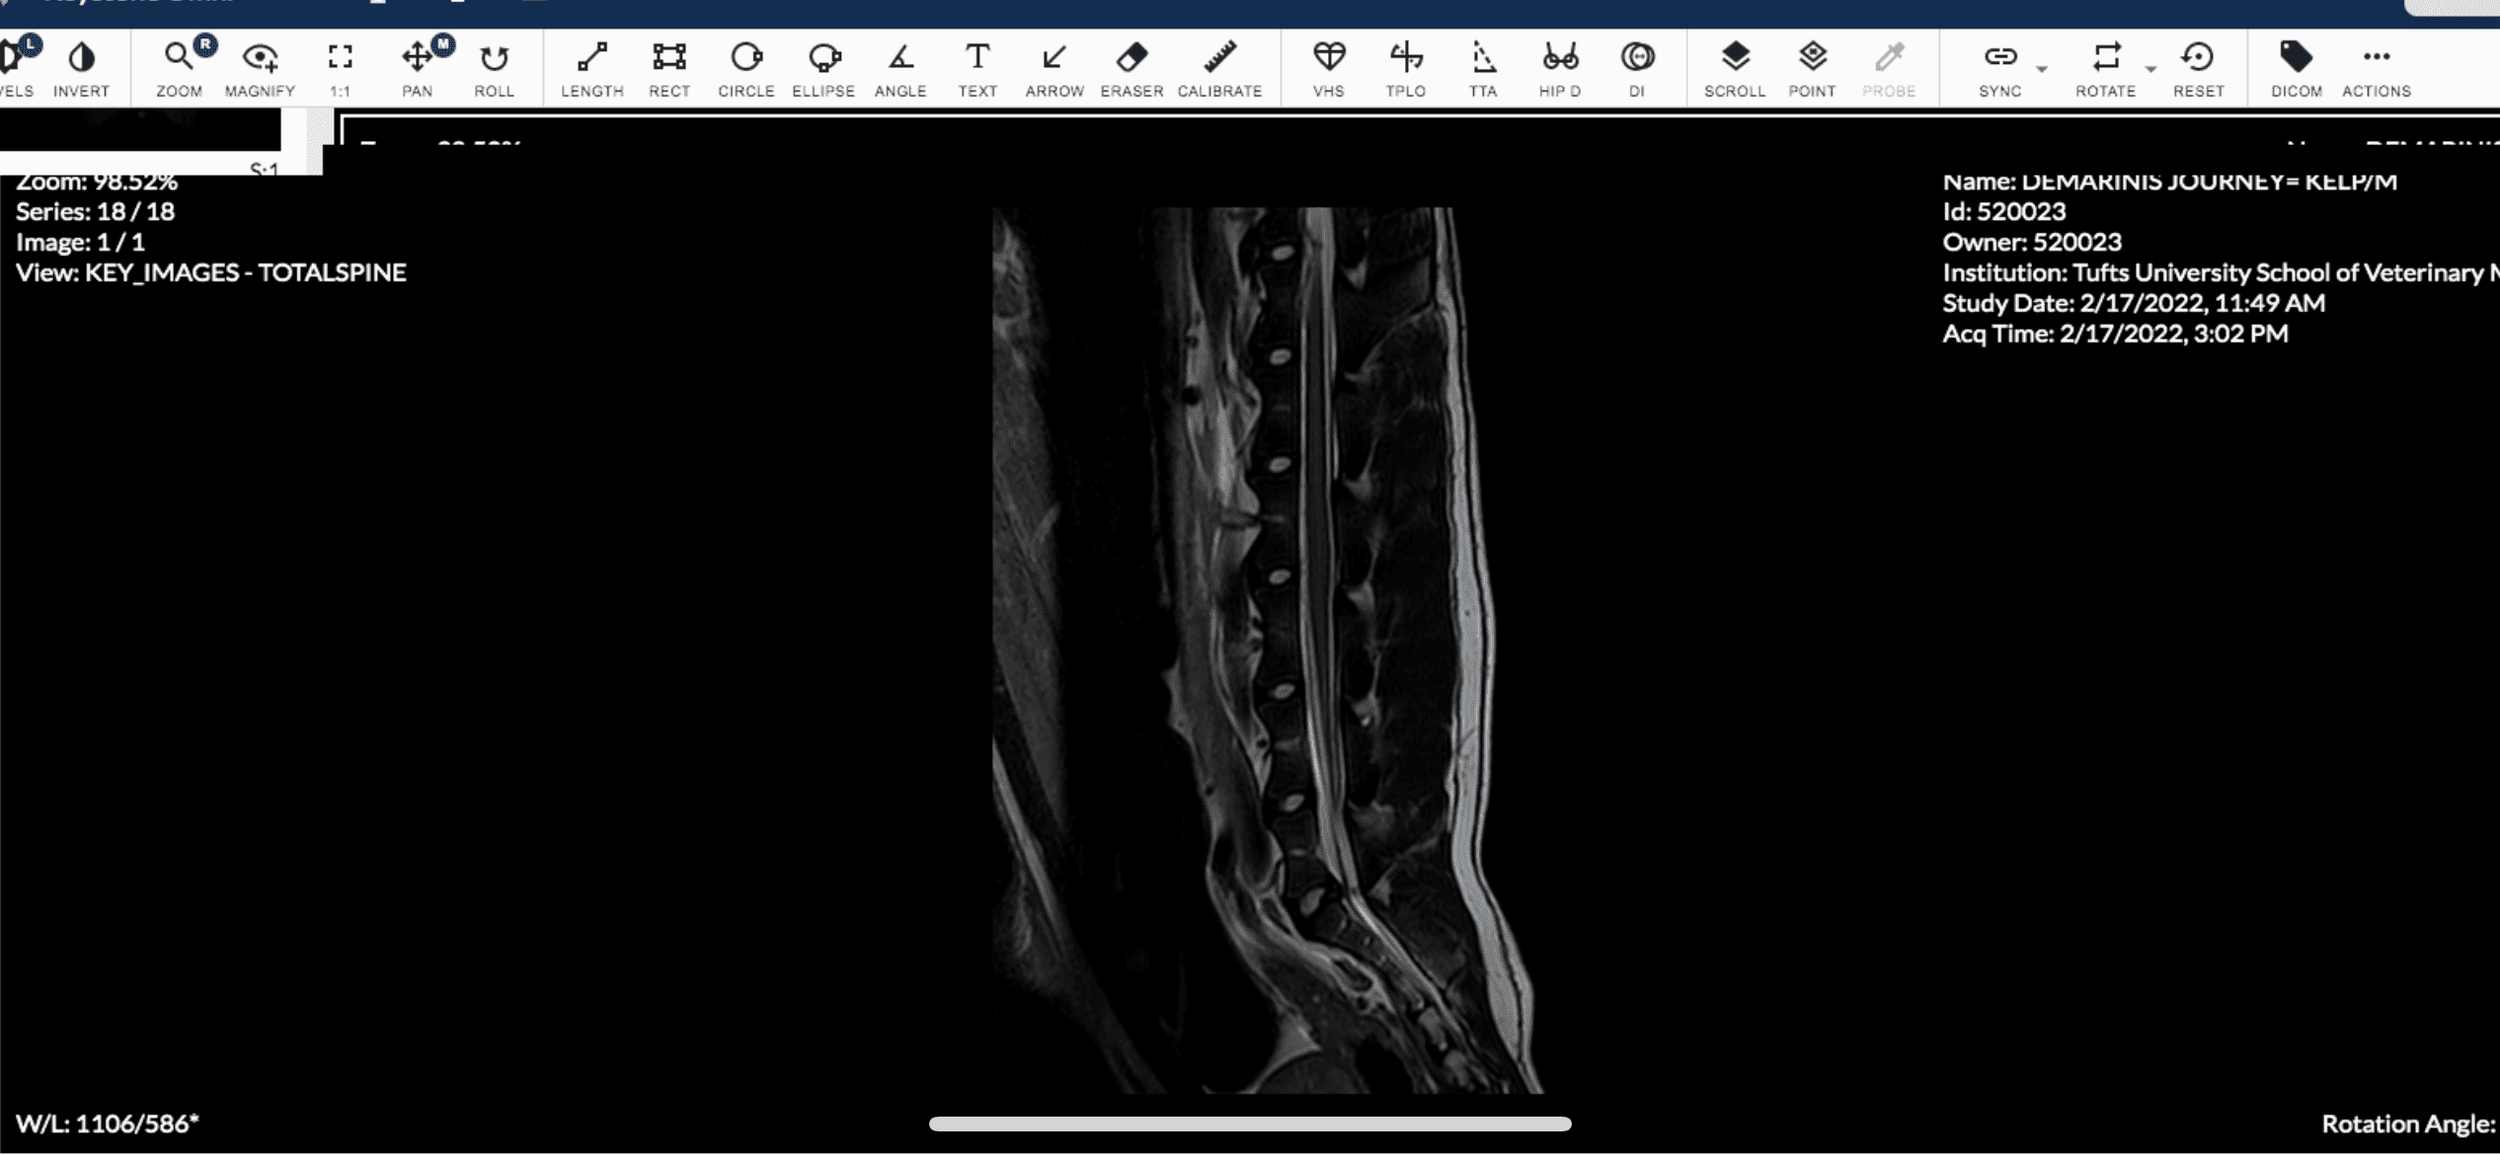

On 2/17/22 at 7:30am I dropped Journey off for his MRI. I was a nervous wreck. At 9:00am a vet technician emailed me asking for the video footage I had of Journey's episodes so that the board certified neurologist could take a look at them. At 3:30pm, the neuro resident called to update me. She said that the neurologist performing the MRI reviewed the videos as well as his brain scan. The brain scan was clear! Nothing abnormal showed up. BUT, the neurologist noticed after observing the videos that Journey seemed to display more of his episodes towards his lumbar/rear area, so the neurologist decided she wanted to do a lumbosacral MRI (an MRI of his lumbar/rear area). They identified that it was very possible he has a rare condition called Tethered Cord Syndrome. They couldn't rule out whether he also had Epilepsy, but based on the findings of the MRI, it seemed that the episodes Journey was having was related to Tethered Cord Syndrome.

Some of Journey's MRI Images of Tethered Cord

Screenshot of Journey's MRI Imagery